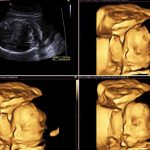

Если по каким-либо причинам осмотр невозможен или нежелателен, может использоваться трансвагинальное ультразвуковое исследование (ТВУЗИ) для измерения длины шейки и оценки состояния внутреннего зева.

Особое место в оценке состояния шейки матки занимает ультразвуковая цервикометрия – измерение длины шейки с помощью трансвагинального датчика. Этот метод наиболее точен для диагностики истмико-цервикальной недостаточности или при оценке риска преждевременных родов.